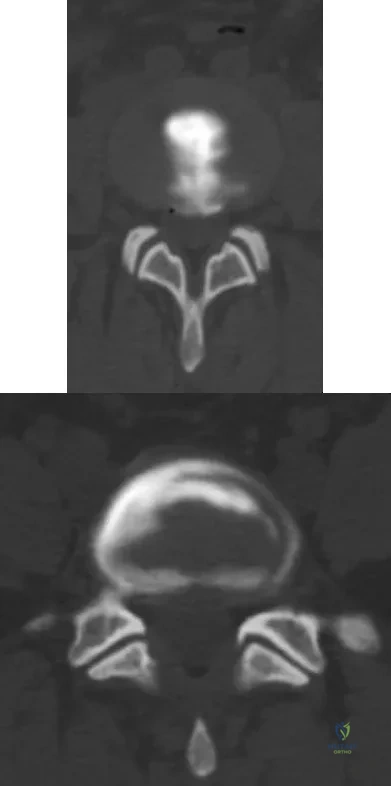

Question 99

A 55-year-old woman with a long history of low back and left lower extremity pain has failed to respond to exhaustive nonsurgical management. MRI scans show bulging and degeneration at L3-4 and L4-5 as well as a normal disk at L2-3 and L5-S1. She undergoes provocative lumbar diskography at L3-4, L4-5, and L5-S1. Post-diskography axial CT images of L3-4 and L4-5 are shown in Figures 6a and 6b, respectively. The injections at L3-4 and L4-5 produce no pain. The injection at L5-S1 produces 10/10 concordant back pain with radiation to the lower extremity. What is the most appropriate recommendation at this time?

Explanation